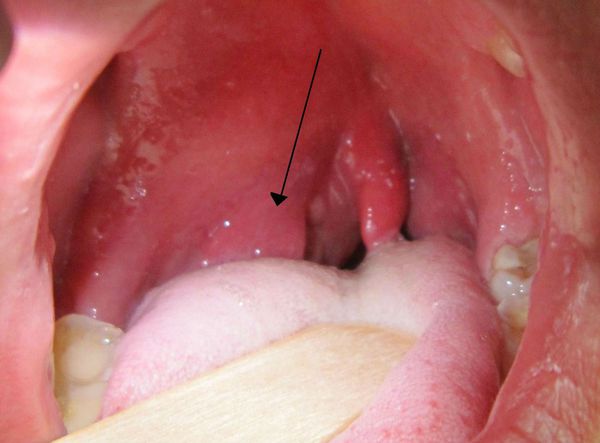

Przy ropniu przestrzeni skrzydłowo-żuchwowej (nagromadzeniu ropy między mięśniami odpowiedzialnymi za ruch żuchwy) u pacjenta występuje gorączka, ból gardła, trudności w połykaniu oraz ograniczone otwieranie ust – czasami niemal niemożliwe. Zewnętrznie obrzęk wokół ogniska zapalnego (obrzęk okołogniskowy) może być niewidoczny. Badanie jamy ustnej jest możliwe dopiero po blokadzie gałęzi ruchowych nerwu żuchwowego (czasowym znieczuleniu umożliwiającym rozluźnienie mięśni). W jamie ustnej zwykle obserwuje się utrudnione wyrzynanie dolnego zęba mądrości oraz zaczerwienienie (przekrwienie) i obrzęk fałdu skrzydłowo-żuchwowego.